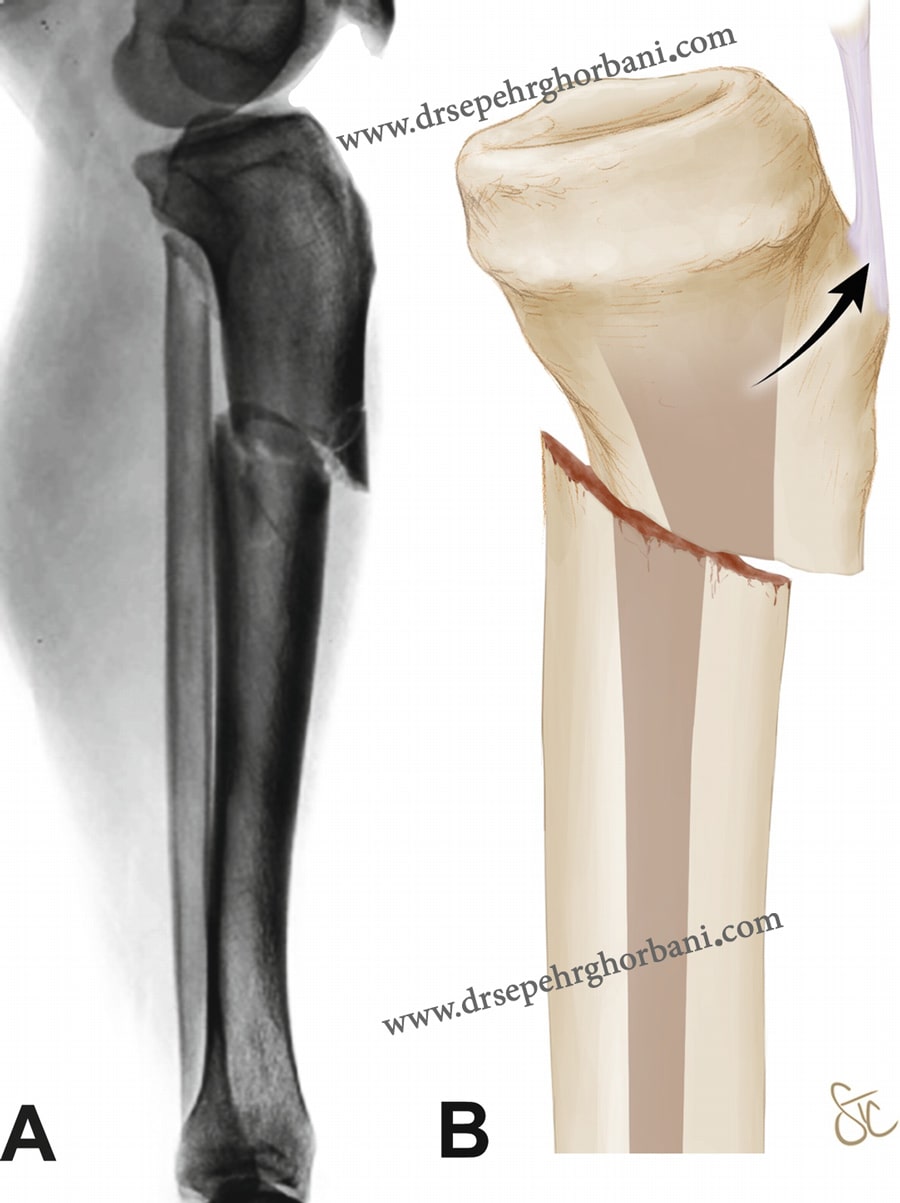

وضعیت بافت های نرم اطراف بعد از شکستگی

آسیب بافت نرم در شکستگی های اطراف زانو از اهمیت حیاتی برخوردار است. ورم و التهاب همراه با تروما می تواند به راحتی منجر به هیپوکسی پوستی و آسیب اضافی به بافت نرم شود. این امر معمولاً منجر به تاول زدن پوست و در بعضی موارد نکروز پوستی و حتی عضلانی می شود. مدیریت در مراحل اولیه درمان باید بر جلوگیری از آسیب بیشتر بافت نرم هنگام انتظار برای ترمیم شکستگی متمرکز باشد.

بی حرکتی زانو و سرما درمانی از متداول ترین روش ها برای کاهش پاسخ التهابی است. بی حرکتی زانو را می توان با بستن آتل یا فیکساتورهای خارجی انجام داد. استفاده از یک رویکرد مرحله ای با استفاده از تثبیت خارجی در الگوهای پیچیده و ضربه های با انرژی بالا، به ویژه در موارد بی ثباتی محوری توصیه می شود.